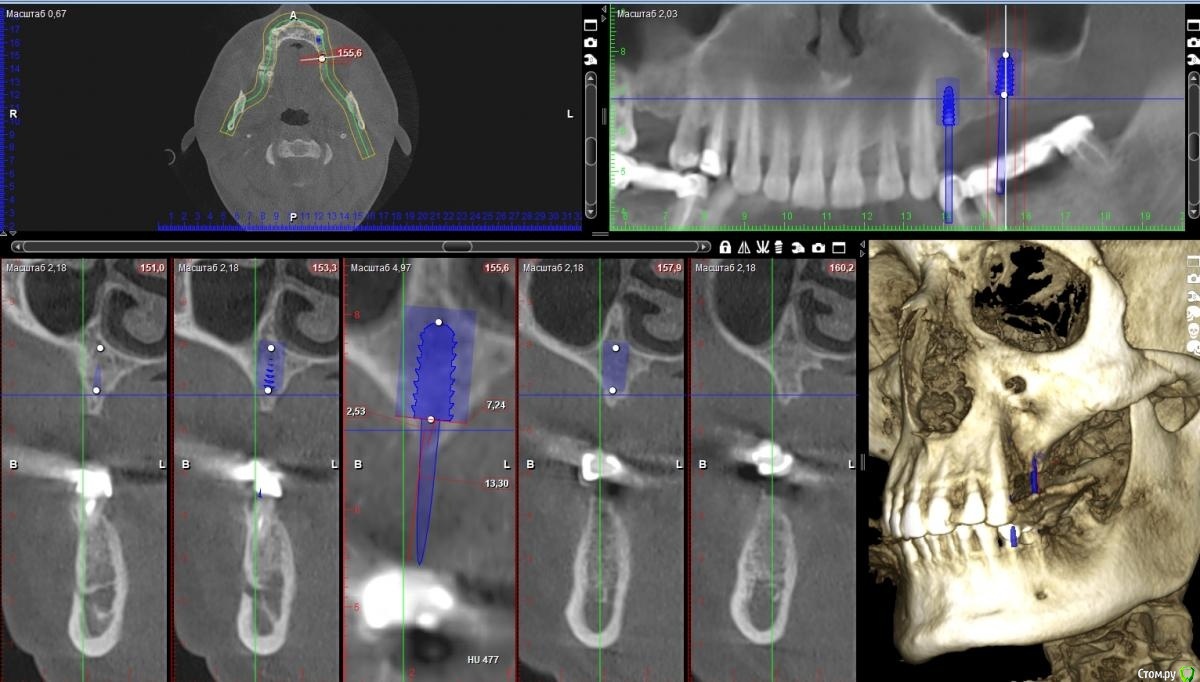

zumanok Опубликовано 28 октября, 2020 Поделиться Опубликовано 28 октября, 2020 Здравствуйте коллеги, обратился пациент с потерей зубов в результате пародонтита. В ходе лечения терапевту удалось улучшить гигиену пациента и на данный момент изменений нет два года. Пациент обратился с вопросом о имплантации. Планирую сделать мост 14-16 Возник вопрос, в области 16 есть возможность установить импл. 4.5 на 10, но от платформы до антагониста получается 14мм. стали бы Вы делать имплантацию без НКР ( что я и хочу сделать) или все таки делать НКР ПТФе мембраной? Благодарю за ответы. Ссылка на комментарий